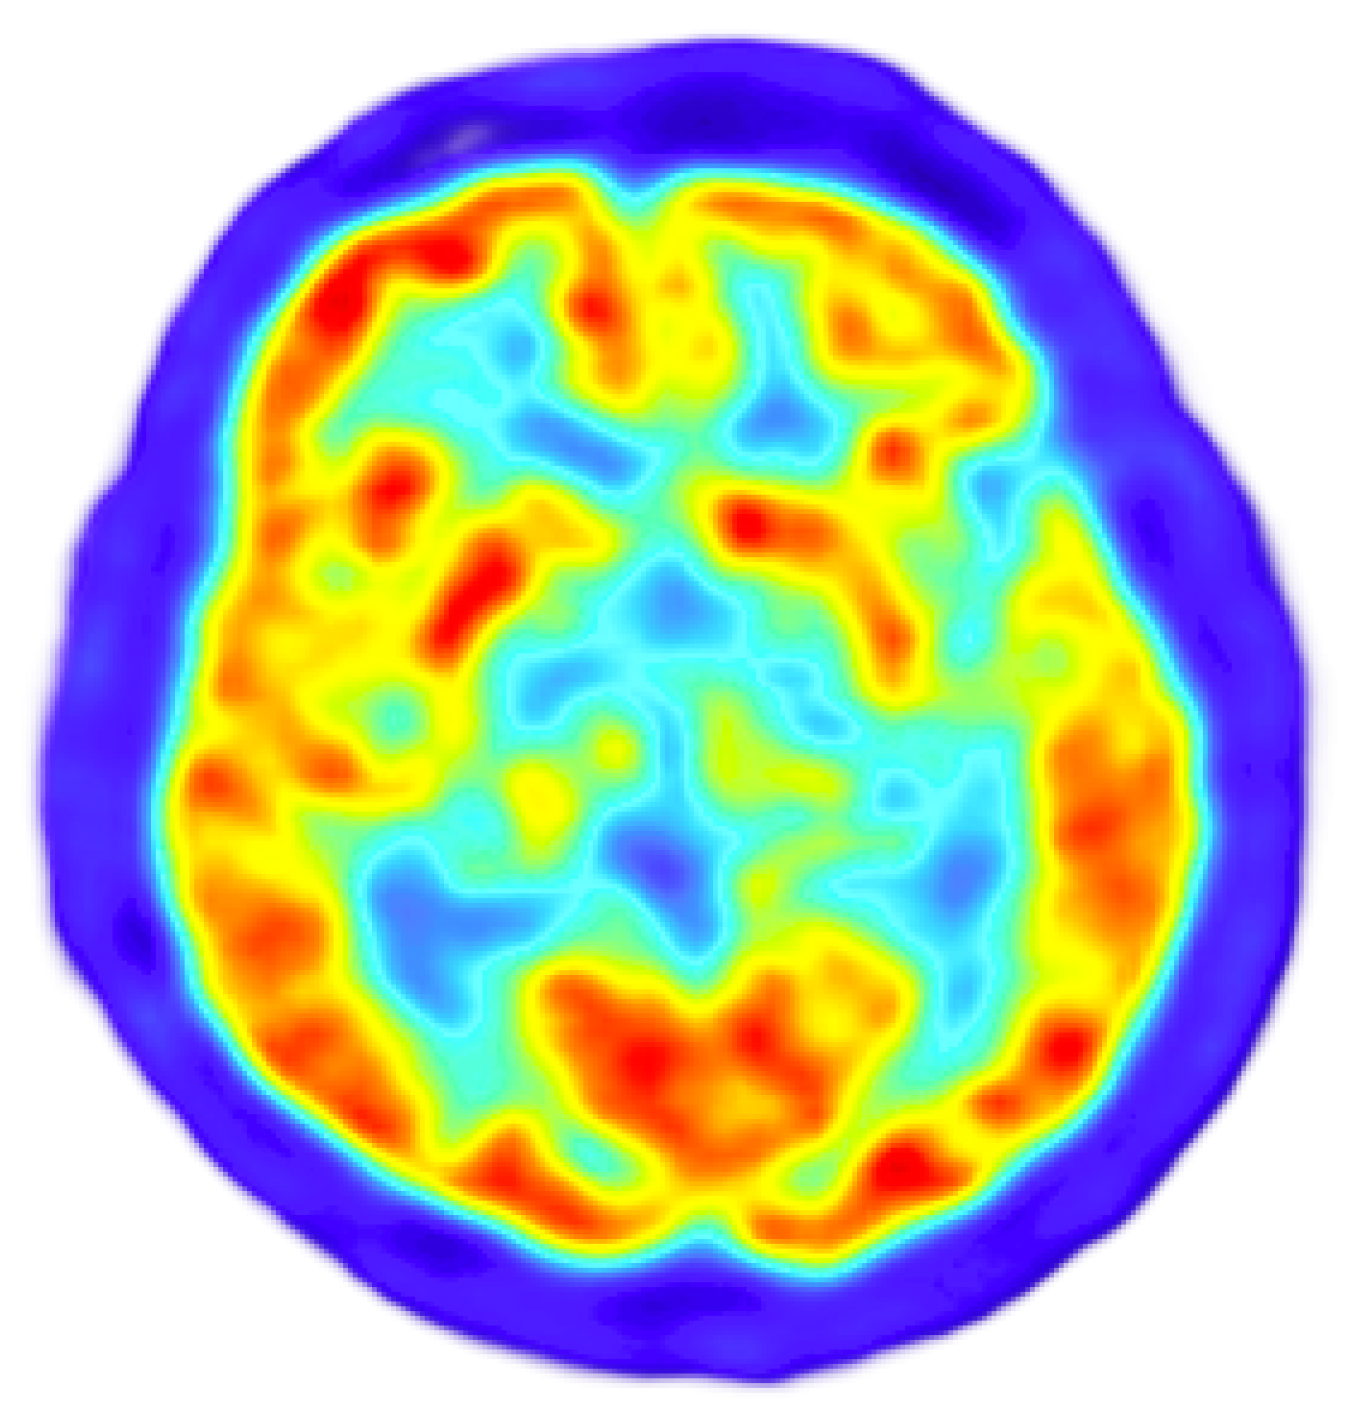

2.6. Positron Emission Tomography